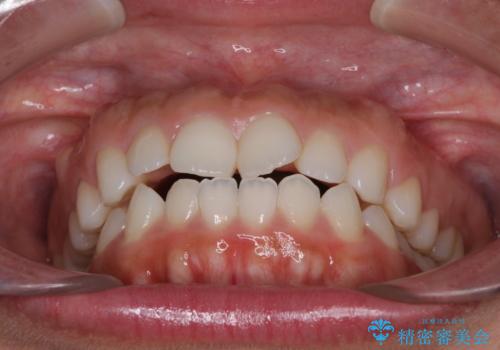

目立たない装置で横顔のシルエットを改善 ハーフリンガルでの抜歯矯正

- 口元の突出感を気にして来院された患者様です。

上下左右の第一小臼歯4本を抜歯して口元を下げる治療計画としました。

表側のワイヤー矯正に比べると治療期間は長く、費用も高額となりますが、どうしても目立たせたくないという方にはお勧めの抜歯矯正です。